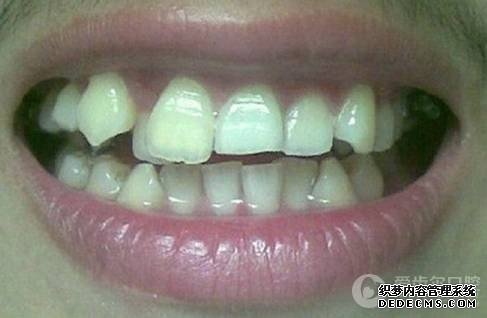

矫正前旧照

矫正前照片

临床诊断:通过3D数字化全景机的拍片检查,患者上下牙排列拥挤,前牙受挤压向内歪斜,咬合关系异常,唇形尚可,颞下颌关节检查未见异常,无蛀牙、牙周疾病症状。经过和患者商量,选定自锁托槽矫正方案,调整牙间隙,恢复牙齿的正常排列,实现正常的咬合关系。